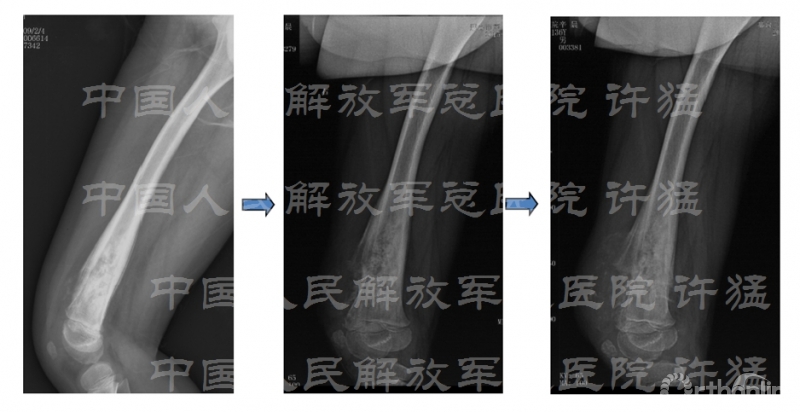

治疗及化疗后影像学检查: